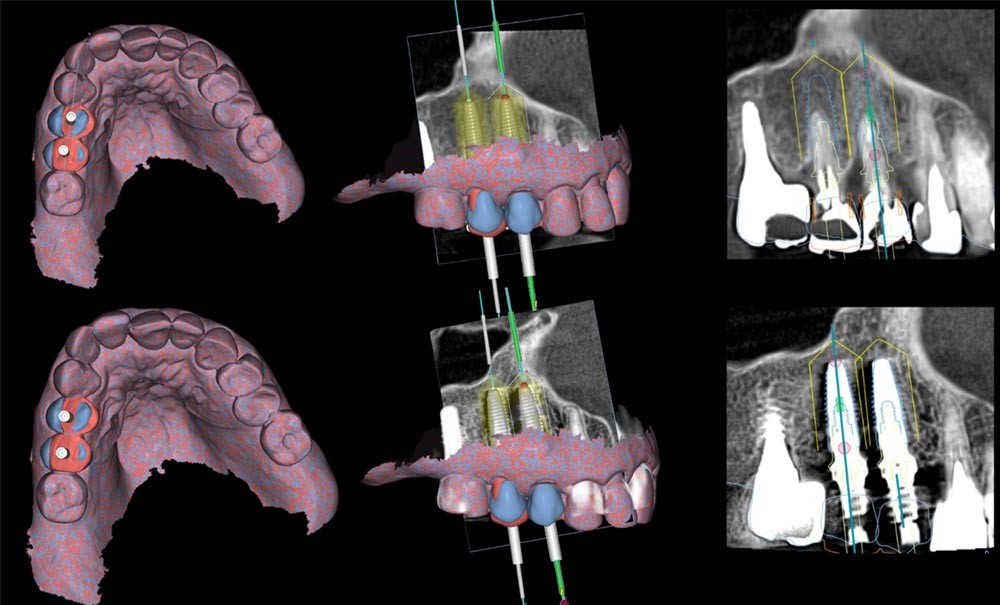

L’intégration des technologies numériques transforme progressivement la pratique de l’implantologie, en modifiant la manière dont les traitements sont planifiés et réalisés. Dans ce contexte, la chirurgie implantaire dynamique assistée par ordinateur (dCAIS) apparaît comme une innovation en phase avec un flux de travail entièrement digitalisé, en offrant un guidage chirurgical précis sans recourir à un guide physique.

La capacité à exécuter fidèlement un traitement planifié repose, entre autres, sur la précision du positionnement implantaire en termes de déviation coronale, apicale et angulaire. Toute déviation peut compromettre l’intégration prothétique, altérer la stabilité des tissus péri-implantaires et favoriser l’apparition de complications biologiques. À travers deux cas cliniques, cet article illustre l’intégration de la navigation dynamique dans un protocole d’implantologie entièrement numérique. Même si des investigations supplémentaires doivent être conduites, les résultats tendent à montrer que la chirurgie implantaire dynamique est une approche prometteuse pour permettre un acte chirurgical conforme à la planification, renforçant ainsi sa pertinence dans des situations cliniques exigeantes.